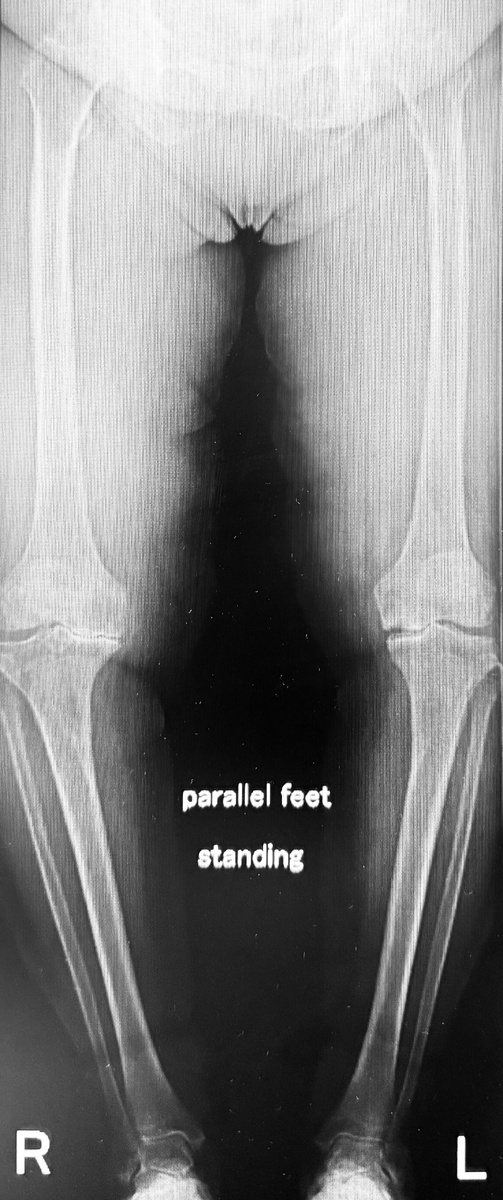

Позавчера выложил здесь видео с моей пациенткой 76 лет. В октябре прошлого года заменил ей один коленный сустав, полтора месяца назад - второй. Всё это на фоне очень выраженной О-образной деформации ног, которая развивалась несколько десятилетий:

Коленные суставы разрушены. Утиная походка. После первой операции одна нога стала ровной и длинной, другая осталась кривой и короткой. Когда выпрямил и удлинил вторую, ноги стали одинаковыми:

Было - стало: